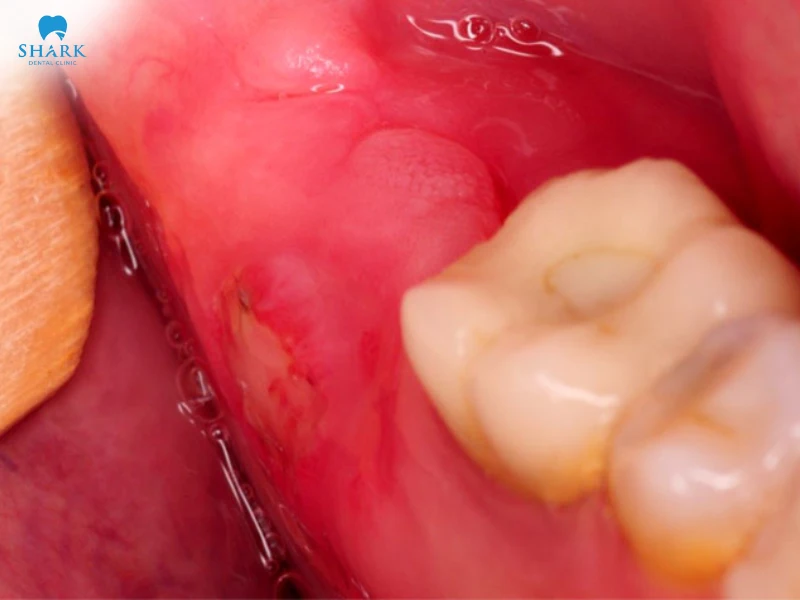

Chảy máu kéo dài

Vết nhổ có thể rỉ máu lâu hơn bình thường, nhất là ở người có bệnh lý đông máu hoặc không tuân thủ hướng dẫn sau nhổ răng.

Nhiễm trùng

Xảy ra khi ổ răng không được giữ vệ sinh tốt hoặc quy trình vô trùng không đảm bảo, gây sưng đau, hôi miệng, thậm chí sốt nhẹ.